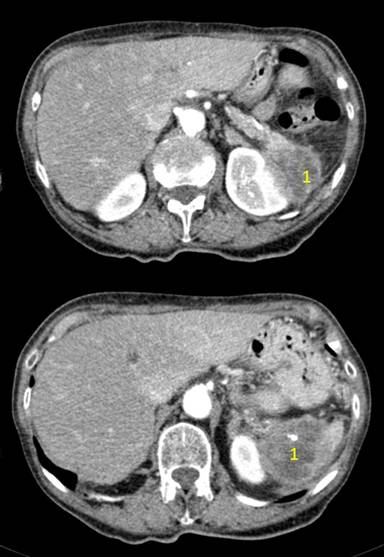

The patient had a past history of hypertension, IgG kappa monoclonal gammopathy and appendectomy, and was diagnosed with an infiltrative mass at the confluence of the tail of the pancreas, spleen, and left kidney. The primary source of the mass could not be determined (Figure 1). Furthermore, in the lower pole of the left kidney a subcapsular lesion suggestive of renal carcinoma was incidentally diagnosed. The cancer staging study ruled out disease dissemination. We decided to perform a surgical en bloc resection including the left kidney, spleen, and left pancreas. The patient was placed in full right lateral decubitus, the habitual position for laparoscopic left nephrectomy.

Figure 1. Preoperative imaging. Abdominal CT showing an infiltrative mass (1) Invading the tail of the pancreas, spleen and left kidney. |